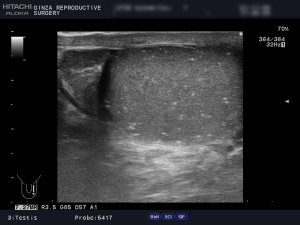

(例)左右の精巣のエコー画像です。

精巣内に腫瘍はありませんが、左右の精巣に白い点が多数見えます。これは精巣機能低下により石灰化してきています。

また、右側に精液瘤9.7mm × 10.1mmがあります。こちらは治療してしますと精巣機能低下につながるので、不妊治療中の場合は、経過観察です。

更に、精巣の大きさに左右差があるのが分かります。左側16ml、右側20mlで、精索静脈瘤により、左側が萎縮しています。